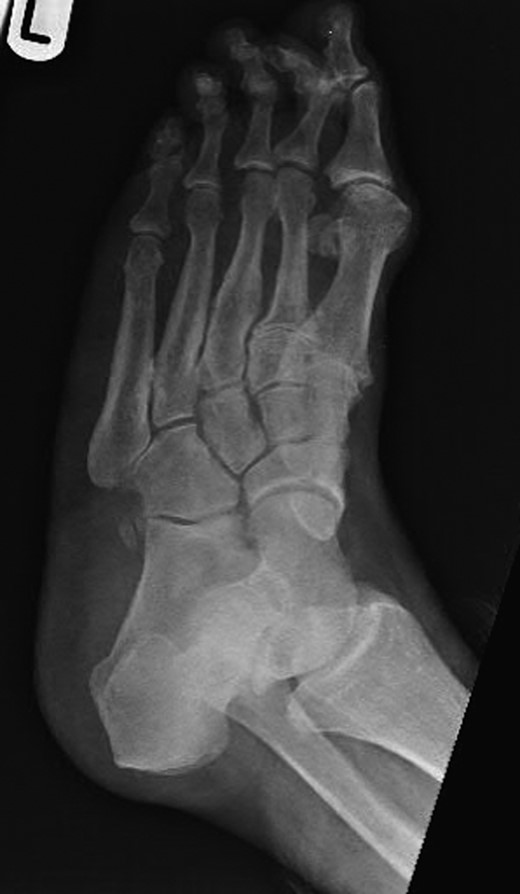

Dorsoplanter, lateral and oblique radiographs demonstrated an additional bone immediately distal to the middle cuneiform articulating with the second metatarsal base and middle cuneiform. Second and third metatarsals were shorßt in comparison with normal (Figs 1–3). Osteoarthritis was seen in all TMTJs and the first MTPJ. A computed tomography (CT) scan confirmed the presence of the additional bone and degenerative joint disease (Figs 4 and 5).

Lateral radiograph of the left foot with the clearly visible additional middle cuneiform.